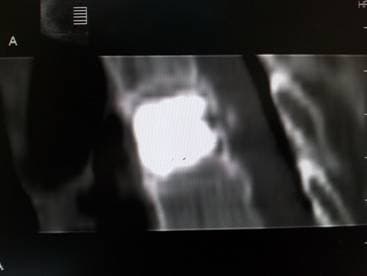

Состояние после вертебропластики

Белый цемент в теле позвонка после процедуры

Цемент в теле позвонка

Распределение костного цемента в теле позвонка